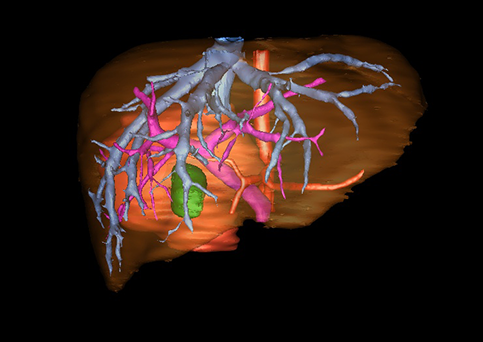

图1 位于肝右的叶肝母细胞瘤, 6个月,男婴

目前常用的检查方法有B超检查、CT、MRI、血管造影等。与其它的腹部肿块的诊断不同,对于小儿肝母细胞瘤血管造影具有重要的意义,可以作为手术前介入治疗的手段,也可为手术提供非常有效的影像学指导,但技术要求高,操作较复杂,且给患儿带来一定的痛苦。近年借助计算机辅助手术系统进行CT原始影像三维重建、手术规划和计算机虚拟手术技术,为精准肝脏手术提供了极为有效的技术支持。

近年来由于数字医学的发展,基于可视化三维重建技术的计算机辅助手术系统极大推进了小儿肝脏肿瘤的精准手术的进步。可以立体透视肝脏解剖、精确掌握肝段的边界、精确测算肝段乃至任意血管所支配的功能体积、准确定位病灶及其与邻近血管的解剖关系,最终对不同手术方案进行比较、筛选和优化。因此,计算机辅助手术规划系统是实现精准肝切除的有力辅助工具,是未来数字外科、精准外科等21世纪外科新理念的重要技术支撑。

计算机辅助手术规划系统具有良好的操作可行性、计算准确性和三维显示效果,可半透明、交互式显示真实的肝内立体解剖关系和空间管道变异,准确计算肝内管道的直径、走行角度,两点间的垂直距离,和任意血管的支配或引流范围等传统二维影像无法获取的信息,有助于实施个体化手术,提高了手术的确定性、预见性和可控性。计算机辅助手术规划系统可直观显示预留肝脏的结构和功能,并可通过虚拟切割功能辅助术者对手术方案进行蹄选和优化,系统评估手术风险和制定对策,改变了部分二维规划的术式和切除范围,使部分二维规划认为不能切除的患者成功手术,提高了手术的根治性、安全性和病变的可切除性,更加符合精准肝脏外科的术前规划要求。详见第11章。

随着计算机技术及影像检查技术的不断发展,以精确的术前影像学和功能评估、精细的手术操作为核心的精准肝切除技术日益受到重视。基于数字医学的计算机辅助手术技术(computer-assisted surgery,CAS)则是实现肝脏精准手术操作的基础。计算机辅助手术系统(CAS)可将术前二维(two dimensional,2D)的CT/MRI影像数据进行三维(three dimensional,3D)重建,建立个体化的肝脏三维解剖模型,清晰显示肝脏内脉管系统的走行及解剖关系,还原病灶与其周围脉管结构的立体解剖构象,准确地对病变进行定位、定性和评估,制定合理、定量的手术方案,实施个体化的肝脏血管取舍分配方案及实施精准肝脏手术。一般认为CAS包括:创建虚拟的患者的图像;患者图像的分析与深度处理;诊断、手术前规划、手术步骤的模拟;术中实时导航。应用本技术后,由于可以更清晰地看出肿瘤的界限,特别是根据肝血管的显影,判断出肿瘤与门静脉及肝静脉的关系以在手术前较准确地估计出手术成功切除的可行性。以往部分根据普通强化CT判断无法手术的病例而被评估为可以成功切除并手术成功。